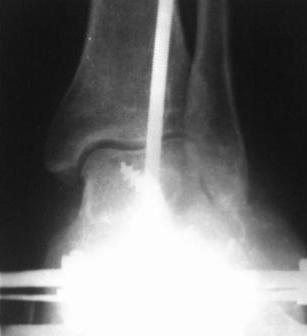

28.02.08г. произведен трехсуставной артродез таранно-пяточного, таранно-ладьевидного и пяточно-кубовидного суставов, с клиновидной остеотомией пяточной кости, с заполнением синуса костными осколками. Фиксация таранно-пяточный стягивающим винтом, таранно-ладьевидный и пяточно-кубовидный спицами, варусная деформация стопы устранена. Для наблюдения за состоянием раны и стопы а также для фиксации и поддержания напряжения произведен к/остеосинтез аппаратом Илизарова.

Почему не сделал чисто подтаранный артродез? Потому что и так нарушена биомеханика стопы, после подтаранного артродеза еще больше нарушается, особенно в суставе Шопара, поэтому артродезировал и его.